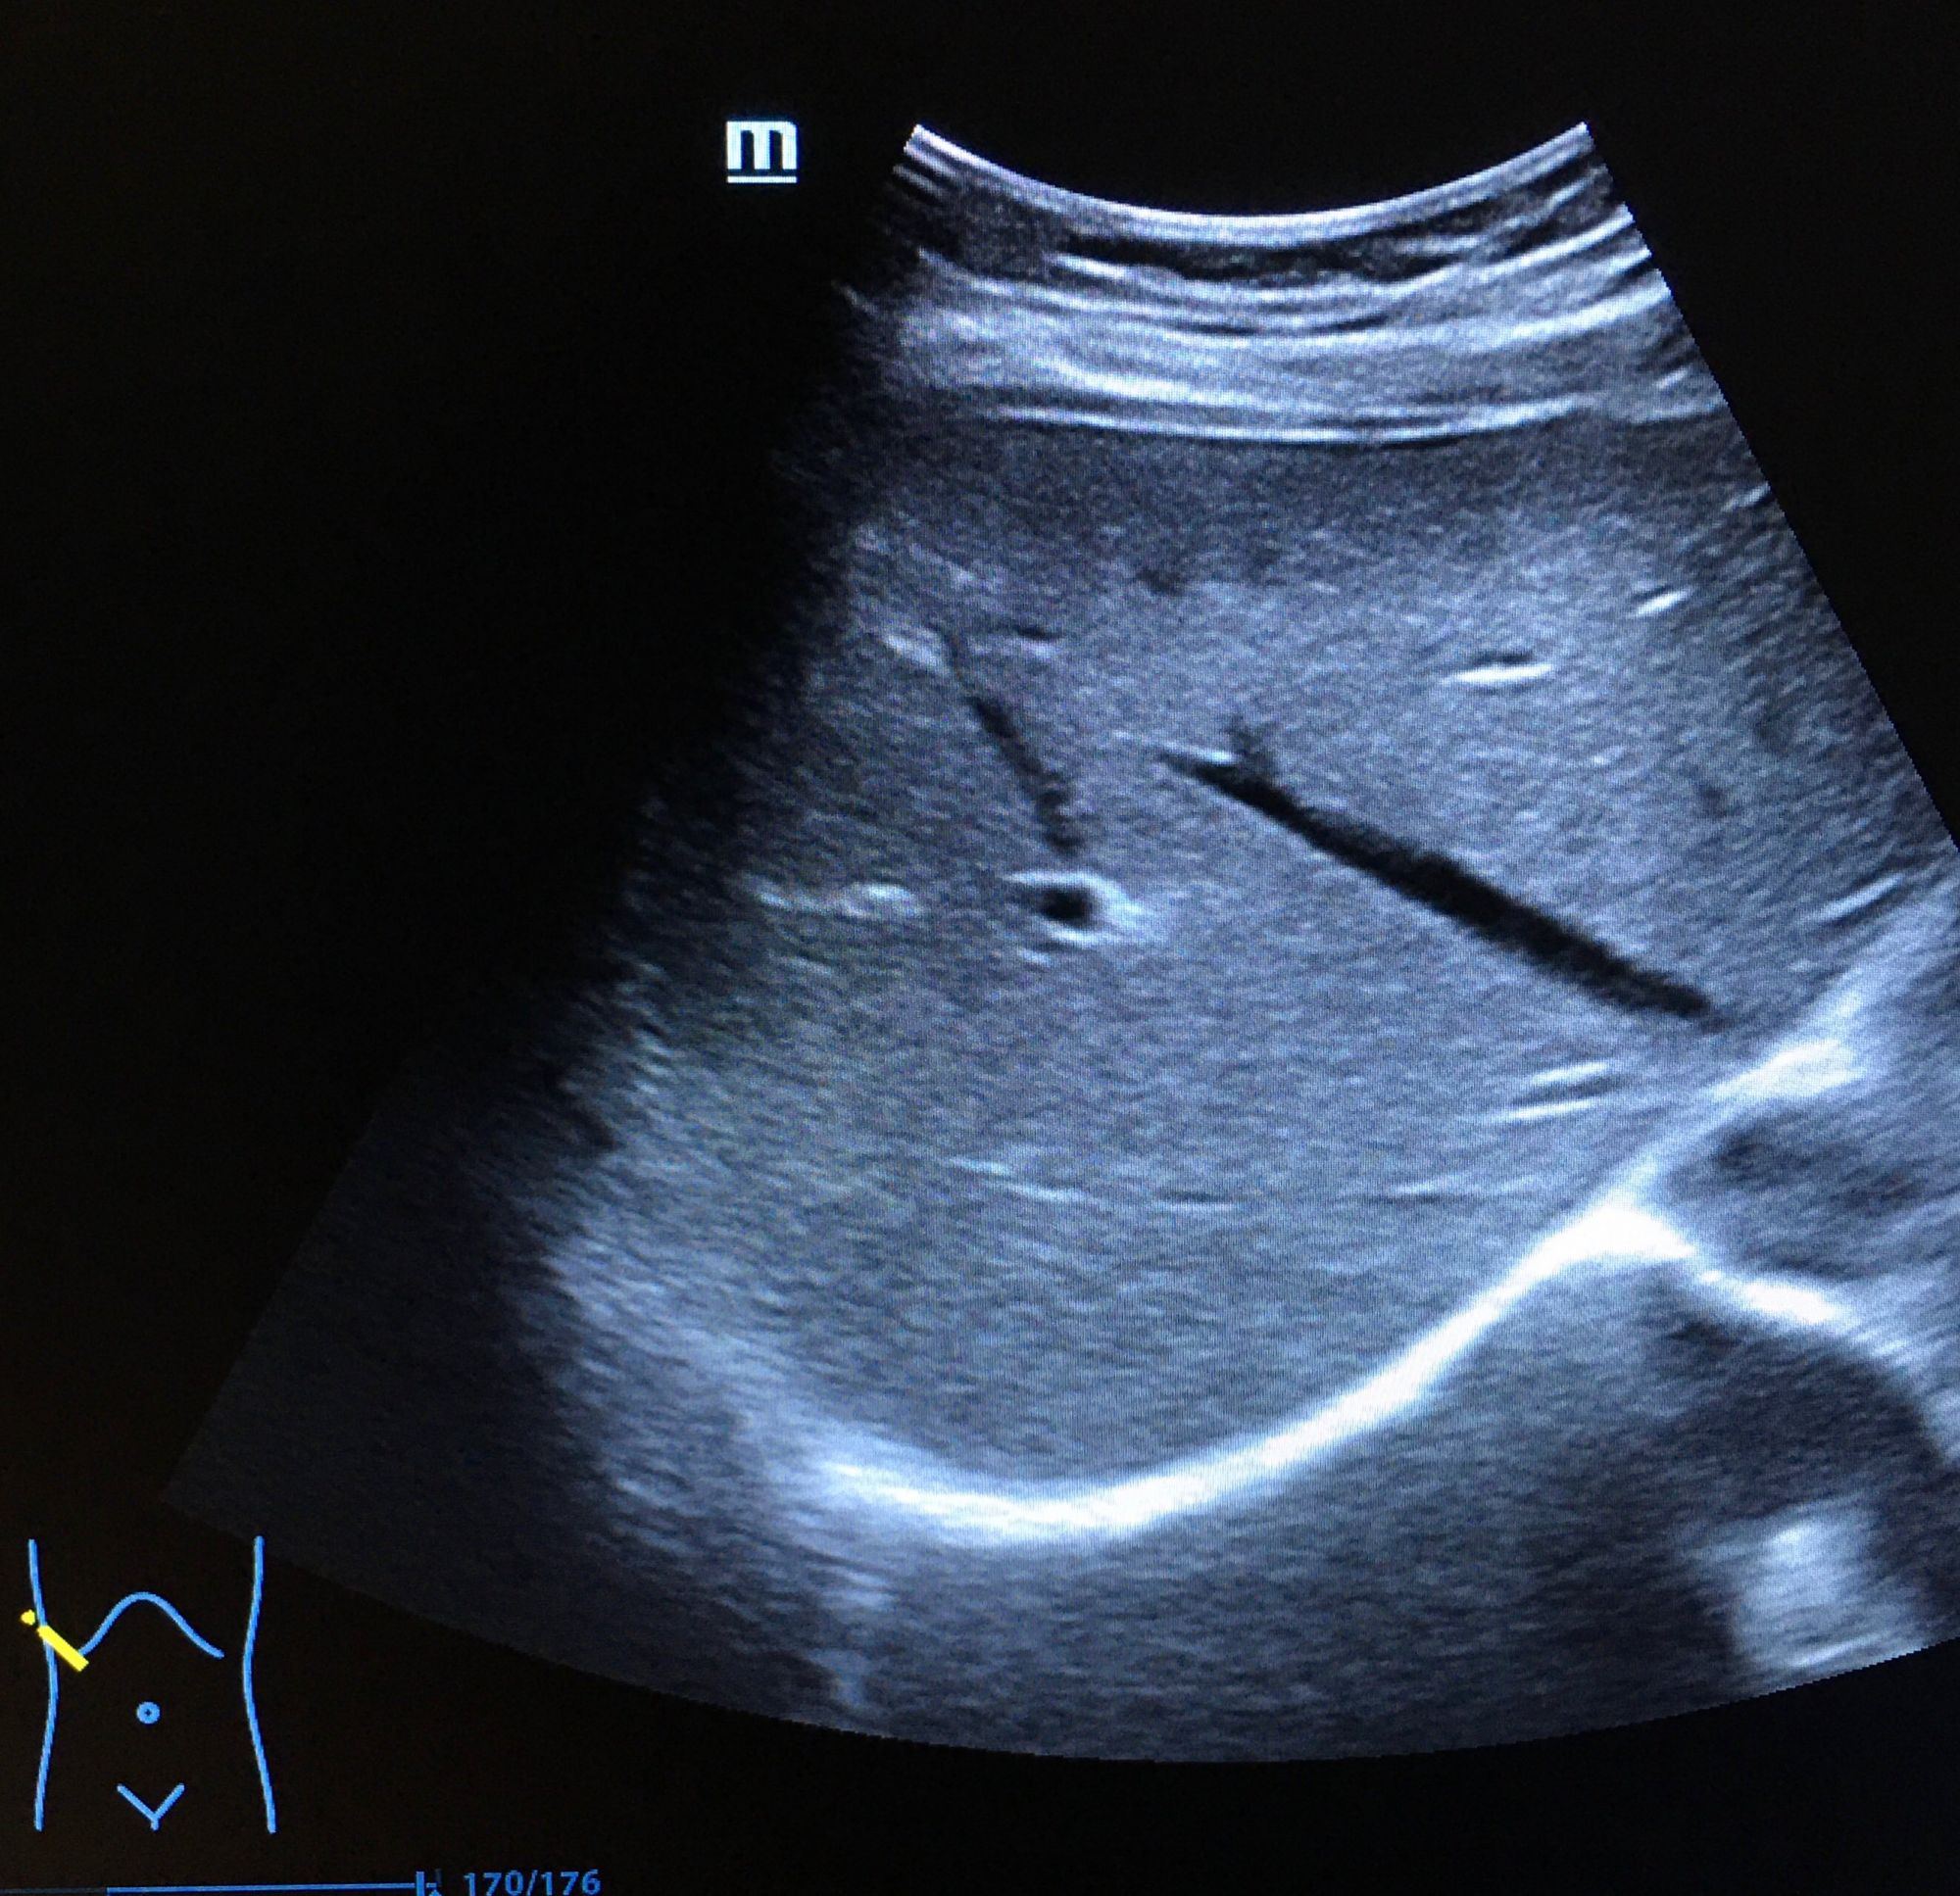

二、超聲成像

是一種基于超聲波的成像技術(shù)。超聲波在生物體內(nèi)傳播時(shí),遇到不同的組織會產(chǎn)生不同的回聲信號,通過分析這些信號可以獲取生物體的內(nèi)部結(jié)構(gòu)和功能信息。超聲成像具有無創(chuàng)、無痛、無輻射等優(yōu)點(diǎn),因此在臨床診斷和生命科學(xué)研究中得到了廣泛應(yīng)用。

超聲成像